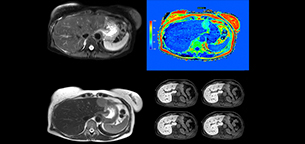

“Fatty liver disease is a common condition. Studies found a prevalence of non-alcoholic fatty liver disease in up to 44% in the general European population [1]. Liver fat cannot be quantified by ultrasound or CT, so biopsy has been the way to quantify fatty liver disease so far,” says Dr. Kukuk. “mDIXON Quant now allows non-invasive quantification of liver fat, which is valuable for both diagnosis and follow-up during dietary changes or therapy, for instance in hepatitis C.”

“The mDIXON Quant fat fraction maps provide quantitative information and also anatomical detail. The sequence is fast, usually taking about 16 seconds, which is just a breath hold for most patients. It definitely improves our efficiency.”

“We have performed a study comparing mDIXON Quant fat percentages with results from histopathology. The correlation with different histologic methods was very good and also the correlation with MR spectroscopy was far above 0.9 – a nearly perfect correlation,” says Dr. Kukuk.

“So, this fast mDIXON Quant sequence allows us to diagnose, quantify, and follow up – that’s the real advantage. Our gastroenterologists were easily convinced, as they are well aware of the limitations of ultrasound and the risks of liver biopsy.”